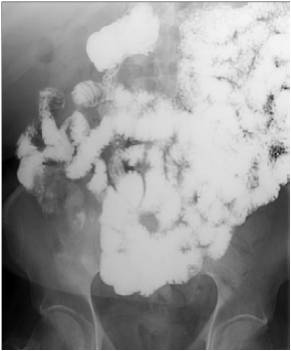

Image

Fig.20.: Follow-through examination

On the abdominal radiograph distension of the small bowel loops and air-fluid levels can be identified. It is important to describe forwarding of the contrast media by time or if mechanical obstruction is seen. Morphology of the intestinal loops could not be assessed with this method. This study is specifically conducted to examine the transit function only.